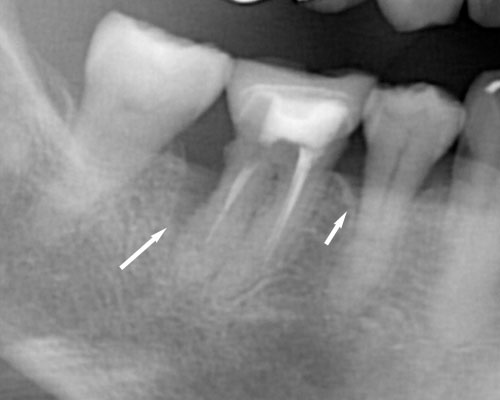

神経がダメになって時間が経っている 神経の入っている管で細菌が繁殖すると、歯の根の先端に炎症を引き起こし、骨の中で膿みの袋がゆっくり膨らみ、やがて骨の外側に膿を出します。見た目は歯と歯茎の境目から1センチあたりの歯ぐきがニキビのように腫れます。多くが「痛みがなく」「ずっと消えない」のが特徴で、スプーンの柄のような硬いもので叩くと他の歯と比べて違和感があります。レントゲンでは根の先端に丸い影を認めます。